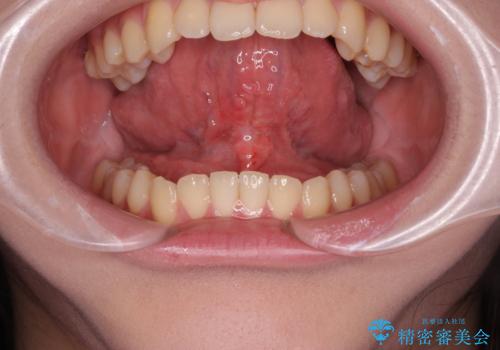

[ 舌の小帯の形成術 ] 滑舌を改善したい

担当医 大元洋佑

![[ 舌の小帯の形成術 ] 滑舌を改善したいの症例 治療前](https://seimitsushinbi.jp/wp/wp-content/uploads/2023/10/IMG_7222-500x350.jpg?v=1697768320)

![[ 舌の小帯の形成術 ] 滑舌を改善したいの症例 治療後](https://seimitsushinbi.jp/wp/wp-content/uploads/2023/10/IMG_7670-500x350.jpg?v=1697768329)